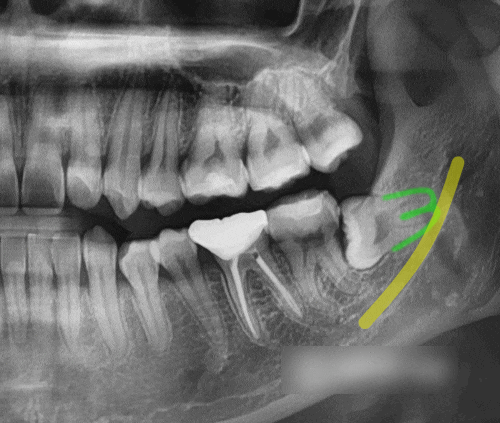

신촌 사랑니 치과 누워있는 매복 제3대구치 발치 신경 손상이 걱정된다면?

안녕하세요, 대표원장 조민기입니다. 많은 분들이 누워 있는 매복 제3대구치 발치 시 신경 손상에 대해 걱...